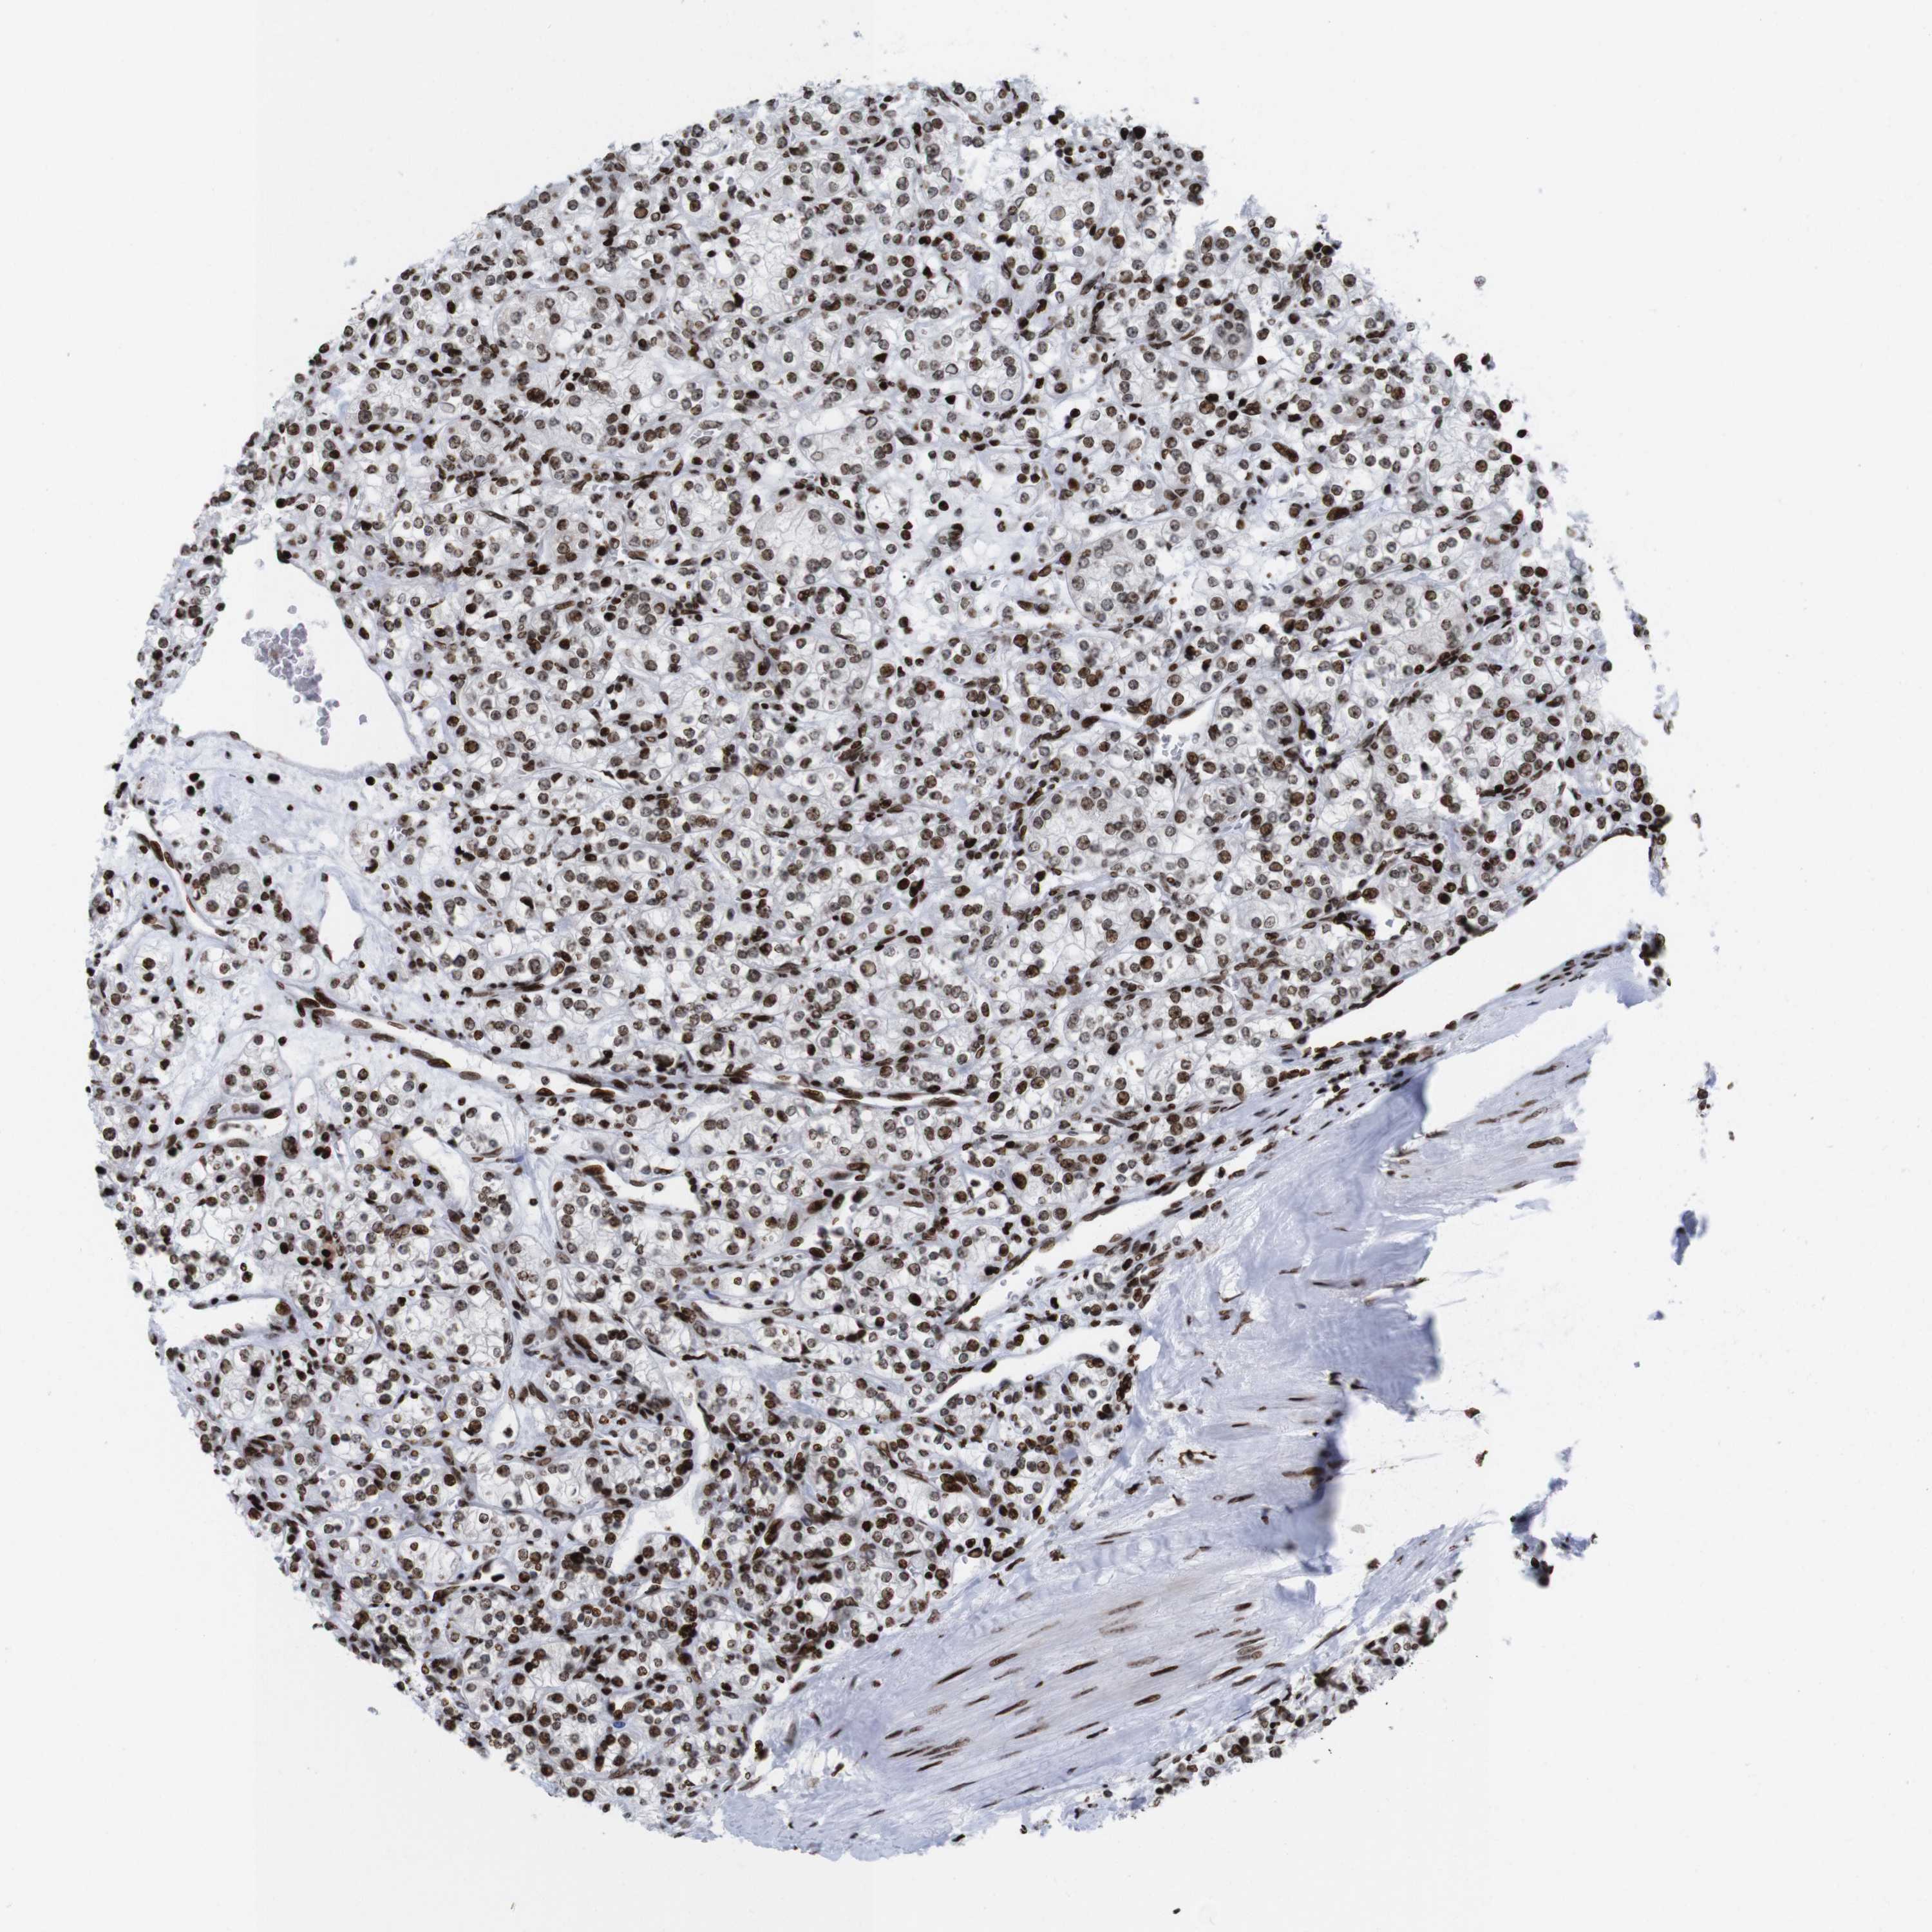

CANCER RENAL CANCER Show tissue menu

KICH TCGA KIRC TCGA KIRC VALIDATION KIRP TCGA PROTEIN RCC CPTAC PROTEIN EXPRESSION